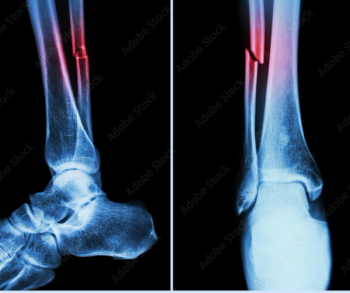

The authors of a new meta-analysis found no significant differences between clinicians and artificial intelligence in diagnosing fractures but conceded that slightly over half of the studies assessed had a high risk of potential bias.